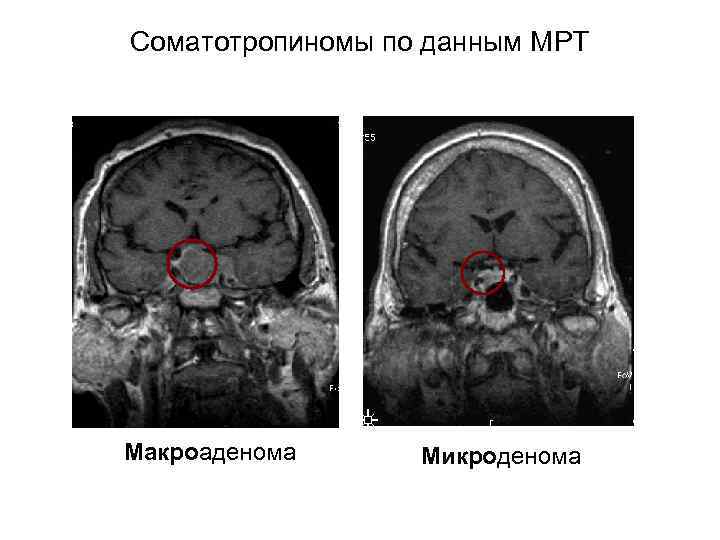

Соматотропиномы по данным МРТ Макроаденома Микроденома

Соматотропиномы по данным МРТ Макроаденома Микроденома